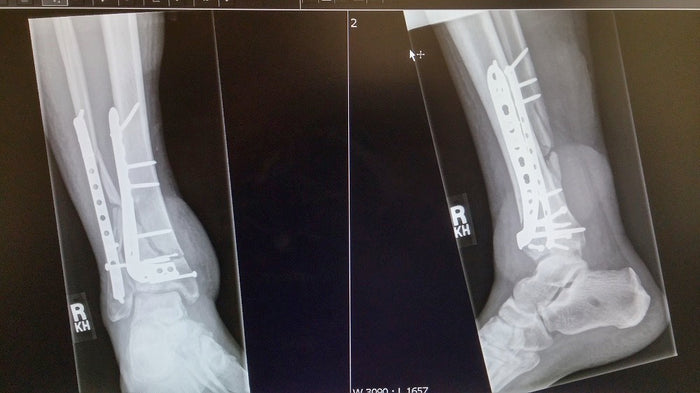

After 13 surgeries to save his broken foot and leg, a Calgary man has invented an alternative to cumbersome crutches. He knew there was a better way. He created it!